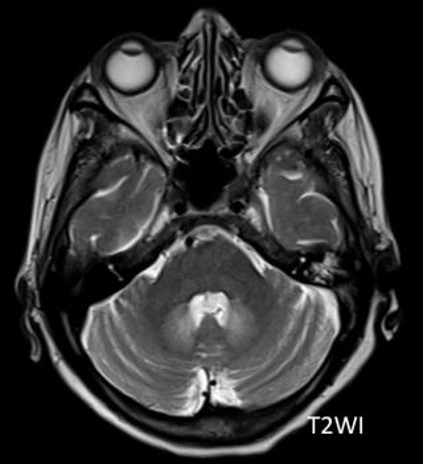

Question: A 56-year-old man with a history of treated liver abscess 1 month ago presents with vertigo, gait ataxia and tremors. MRI is as shown below. What is the diagnosis?

Correct Answer: Metronidazole toxicity

Explaination: Metronidazole is well known to cause brain toxicity irrespective of the dose and duration of intake<br>Neurologic toxicity has been reported, especially if the dosage exceeds 2 grams per day for a prolonged period or if the cumulative dose exceeds 20 gramsIn<br> an acute setting, metronidazole toxicity typically presents with cerebellar dysfunction (75% of cases), confusion and altered sensorium (33%), and seizures (13%). On MR imaging, 93100% of cases show involvement of the cerebellum, particularly at the dentate nuclei regions<br>The corpus callosum, midbrain, pons, and medulla are among the less-involved locations.